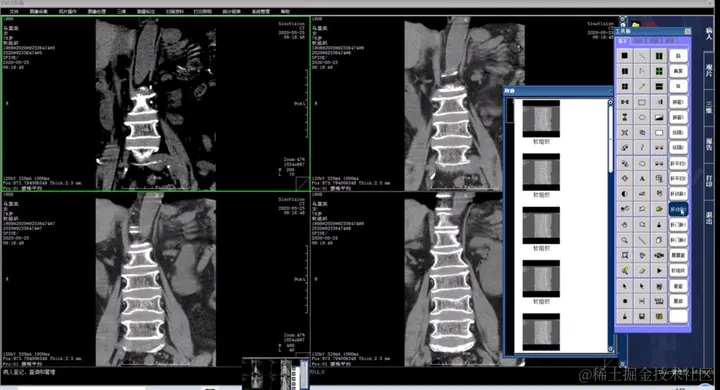

一套基于VC + MSSQL开发的PACS系统源代码,医学影像PACS系统,全称为Picture Archiving and Communication Systems,即医学影像归档和通信系统。它是应用在医院影像科室的系统,主要的任务是将日常产生的各种医学影像,包括核磁、CT、超声、X光机、红外仪、显微仪等设备产生的图像,通过各种接口(如模拟、DICOM、网络)以数字化的方式海量保存起来。当需要时,在有相应授权的情况下,能够快速地调回使用,还提供了一些辅助诊断管理功能。PACS系统是集影像采集传输与存储管理、影像诊断查询与报告管理、综合信息管理等综合应用于一体的综合应用系统。

PACS系统采用C/S架构设计,基于DICOM格式图像传送,JPEG2000无损压缩,可在PDA上使用,包括查询和办公,生成PDF格式报告。提供图文PDF版报告在网上供病人或医生查阅,而非所有原始图像数据,可直接提供给病人(可采用光盘介质或电子邮件)。